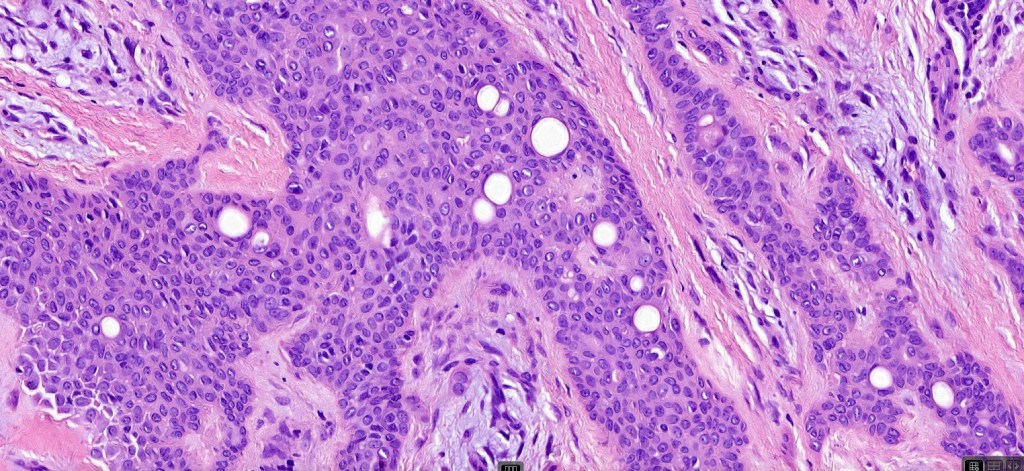

•Well circumscribed unencapsulated, nodular/multinodular silhouette composed of an admixture of epithelial & mesenchymal elements

•Mixed epithelial component including nests & cords of epithelium with abundant, eosinophilic cytoplasm & small vesicular nuclei

•Clear cell change

•Ductal differentiation

•Cribriform/retiform appearance occasionally evident

•Mitoses very rare or absent

•Plasmacytoid myoepithelial cells; clear cell change

•Myxoid change

•Chondroid foci